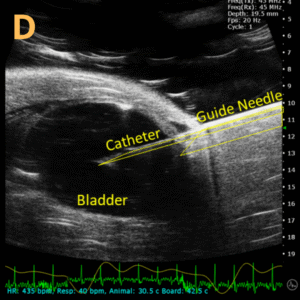

Ultrasound-Guided Bladder Catheterization D